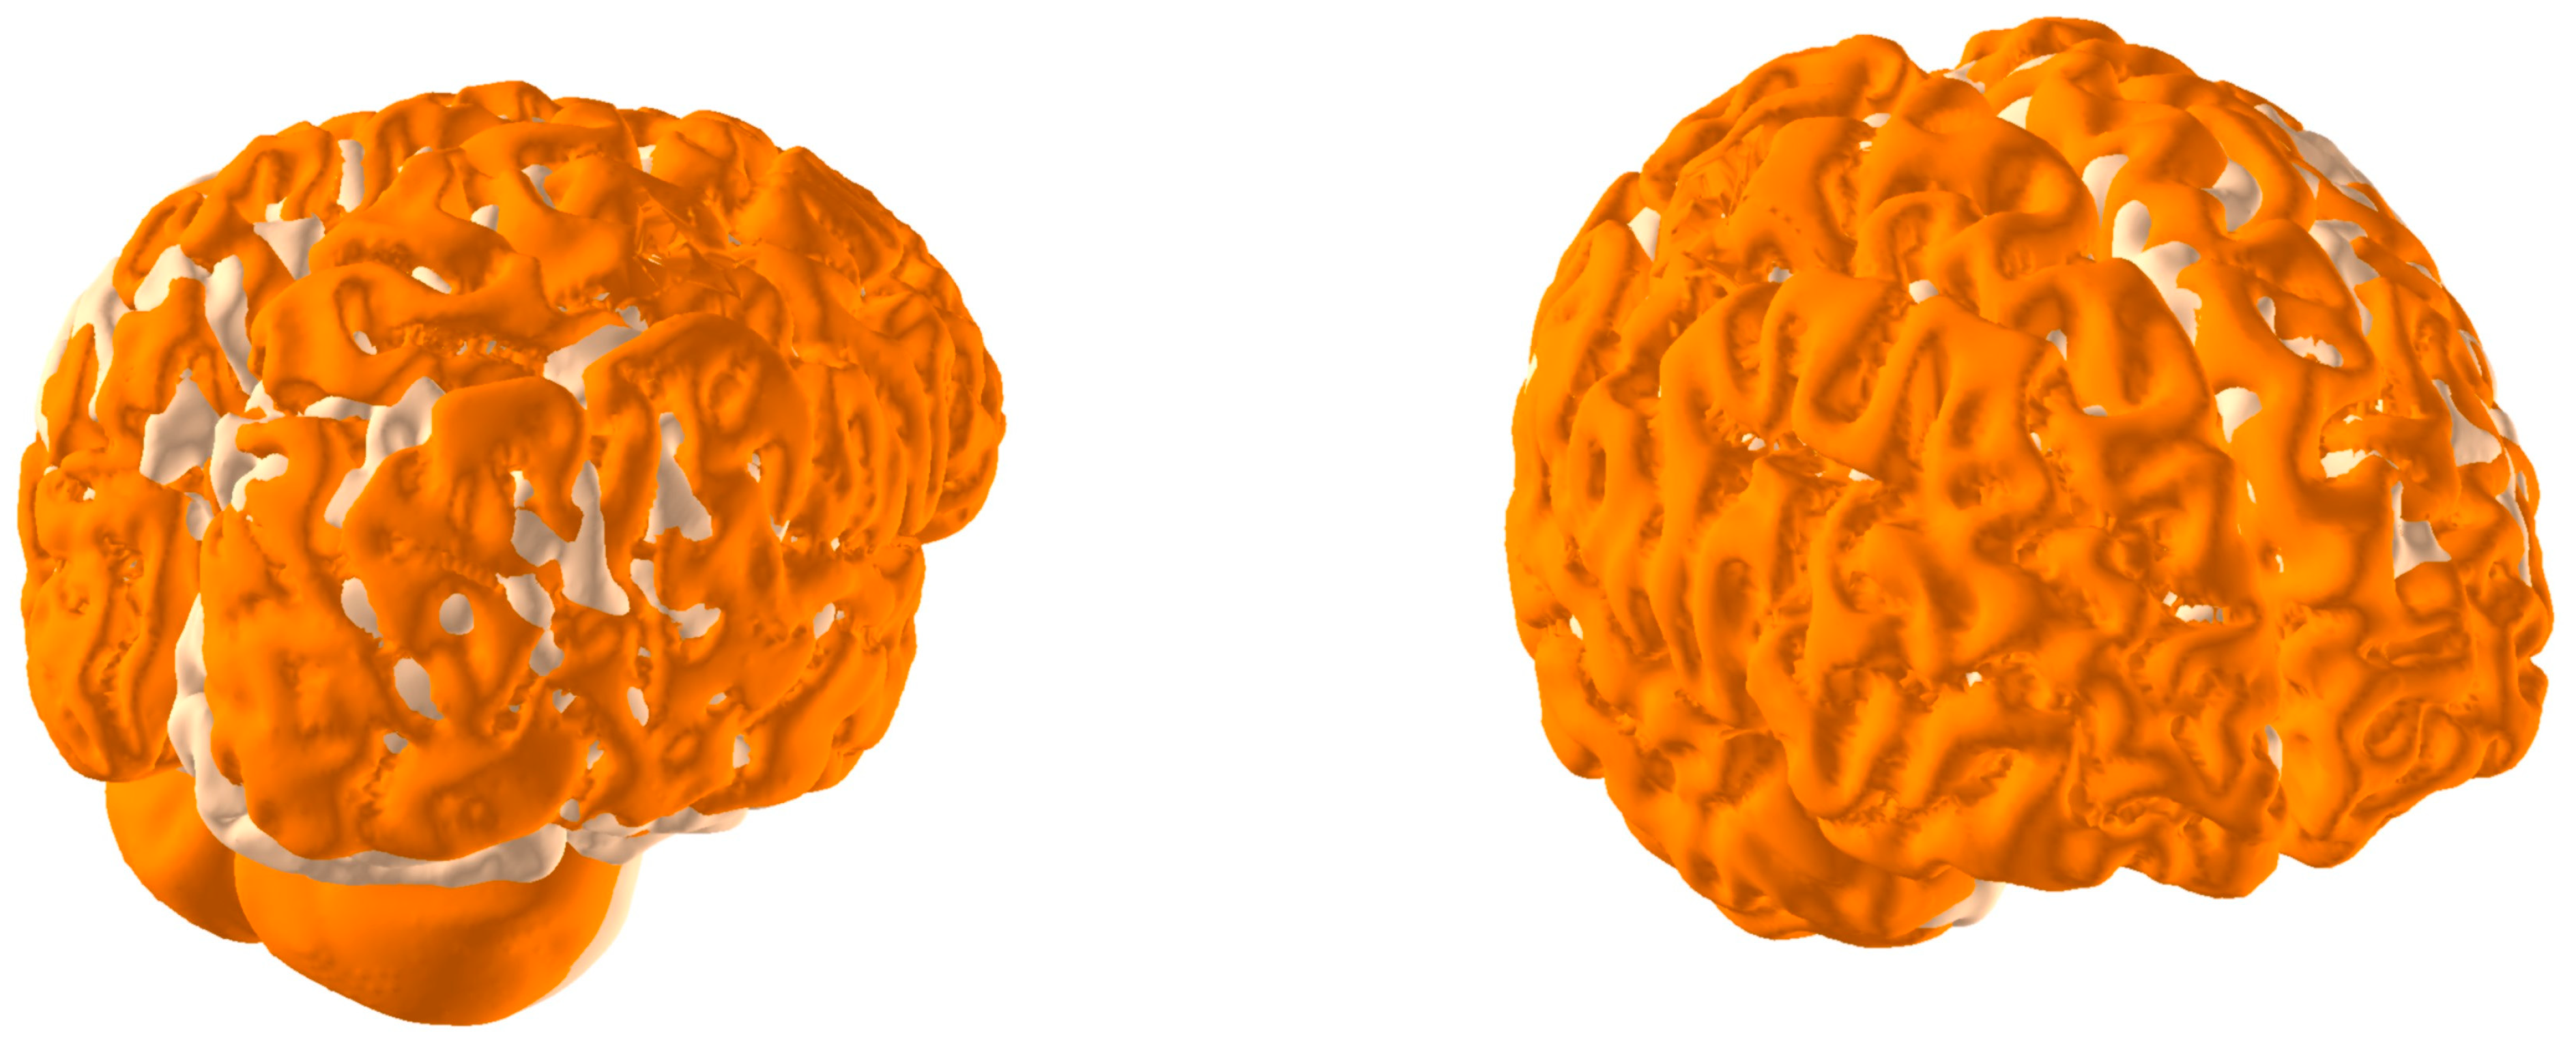

Brain Physical Differences

| Brain Parameters (White and Grey Matter) | Young Adults (28 y)  | Senior (77 y) | Difference (Young Adult vs. Senior) | Comments |

| Brain Volume | 1.0406 [dm3] | 0.98088 [dm3] | 5.7% | Young Adults: On average, young adults tend to have larger brain volumes compared to older adults, with a ~6% difference. This is largely due to ongoing brain development and growth during childhood and adolescence [40]. Senior Adults: Brain volume typically decreases with age. This reduction can be attributed to factors such as loss of neurons and their connections, as well as changes in brain structural integrity. This decrease in volume can affect various cognitive functions. |

| Brain Area | 165,893.3 [mm3] | 1,619,62.1 [mm2] | 2.4% | Young Adults: Younger individuals generally have a larger brain area compared to older adults, with a ~2% difference. The brain area encompasses the surface of the brain, which is important for processing information and facilitating communication between different brain regions. Senior Adults: Over time, there may be a slight reduction in the brain’s surface area. This could be related to the gradual decline in cognitive functions, such as memory and processing speed, experienced by some older individuals. |

| Brain Mass | 1.18 [kg] | 1.02 [kg] | 13.3% | Young Adults: Young adults typically have greater brain mass compared to older adults, with a ~13% difference. Brain mass is closely related to brain volume and is largely responsible for the organ’s overall functionality. Senior Adults: As individuals age, there is often a decline in brain mass, primarily due to a decrease in the number of neurons and synaptic connections. This mass reduction can contribute to age-related cognitive decline. |